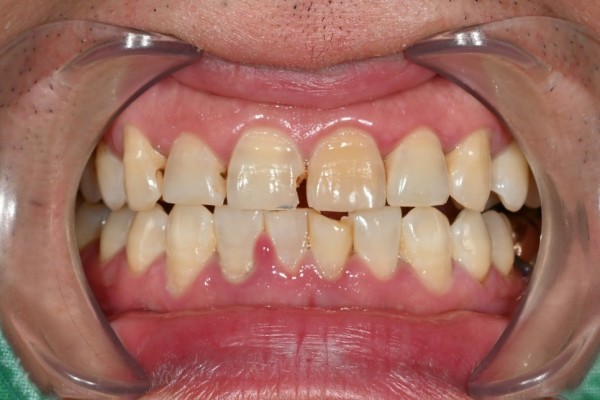

최근 20대 후반 직장인께서 앞니 파절로 내원하셨습니다.

위쪽 앞니와 아래쪽 앞니 일부가 깨져 나간 상태였는데요.

파절된 부분이 눈에 띄어서 일상생활에 불편함이 크다고 하셨습니다.

상태 파악을 위해 구강 내 검진과 엑스레이 촬영을 진행했습니다.

검사 결과 상악 우측 중절치와 하악 좌측 중절치에 파절이 확인되었죠.

다행히 치아 뿌리나 신경에는 문제가 없었습니다.

이런 경우에는 레진을 이용한 수복 치료로 충분히 회복이 가능합니다.